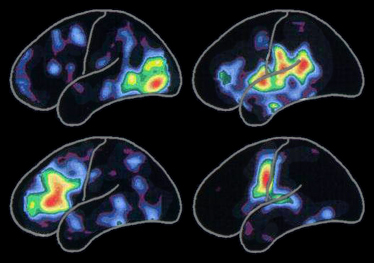

Na przedstawionym obok obrazie mózgu, wykonanym metodą pozytronowej tomografii emisyjnej, widoczne są typowe modele aktywności mózgowych powiązanych z:

Najwyższa odnotowana aktywność zaznaczona jest na czerwono i zmniejsza się przechodząc przez kolejne kolory tęczy, od żółtego do niebiesko-fioletowego.

Niektóre modele aktywności z czasem ulegają zmianom, zależnie od zawiązywania nowych znajomości, zdobywanych doświadczeń lub nabywanych umiejętności. Modele te zmieniają się również w chwili, gdy choroba Alzheimera lub podobne do niej zaburzenia pracy układu nerwowego, niszczą neurony lub połączenia nerwowe pomiędzy komórkami.